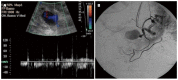

Orthotopic liver transplantation (OLT) represents a major treatment for end-stage chronic liver disease, as well as selected cases of hepatocellular carcinoma and acute liver failure. The ever-increasing development of imaging modalities significantly contributed, over the last decades, to the management of recipients both in the pre-operative and post-operative period, thus impacting on graft and patients survival. When properly used, imaging modalities such as ultrasound, multidetector computed tomography, magnetic resonance imaging (MRI) and procedures of direct cholangiography are capable to provide rapid and reliable recognition and treatment of vascular and biliary complications occurring after OLT. Less defined is the role for imaging in assessing primary graft dysfunction (including rejection) or chronic allograft disease after OLT, e.g., hepatitis C virus (HCV) recurrence. This paper: (1) describes specific characteristic of the above imaging modalities and the rationale for their use in clinical practice; (2) illustrates main imaging findings related to post-OLT complications in adult patients; and (3) reviews future perspectives emerging in the surveillance of recipients with HCV recurrence, with special emphasis on MRI.